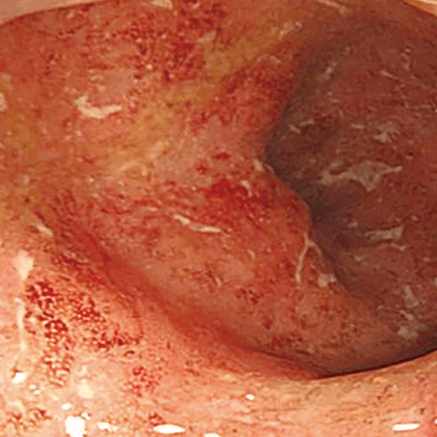

Выраженная активность воспалительного процесса:

yazvennyi_kolit.png

Выраженная активность

Гиперемия и отек

диффузные

Зернистость

выражена

Сосудистый рисунок

отсутствует

Кровоточивость

субэпителиальные геморрагии + выраженная спонтанная ранимость

Эрозии

множественные

Язвы